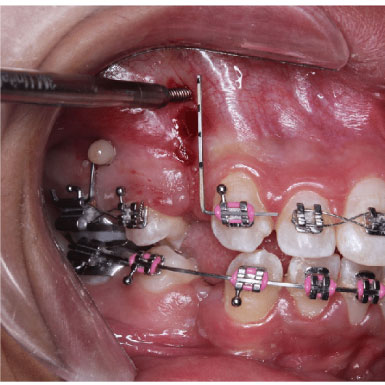

TADs also facilitate molar uprighting and distalization, enabling corrections that enhance occlusal function and aesthetics.

Finally, TADs play an important role in closing open bites, where the front teeth do not touch when the mouth is closed. By providing skeletal anchorage, TADs support the intrusion or extrusion of specific teeth to achieve bite closure. This precise force application helps correct vertical discrepancies and improves both function and appearance, with fewer side effects than traditional methods like headgear or elastics. The versatility and minimally invasive nature of TADs make them an essential component in modern orthodontic approaches for managing challenging bite and alignment issues.